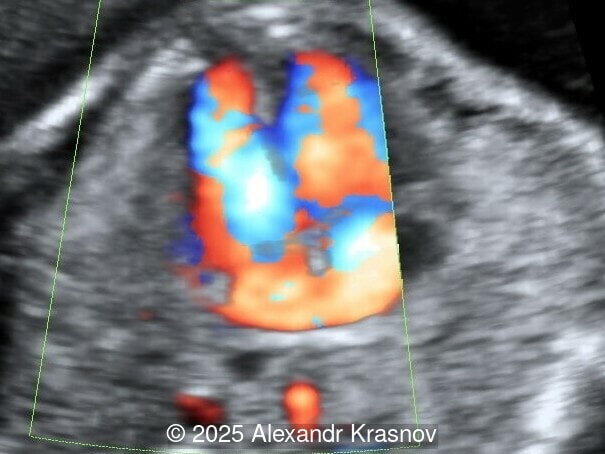

Image 1

Our ultrasound showed biometry data corresponding to 21 weeks of gestation. During echocardiography, an abnormal drainage of the pulmonary veins was detected in which the pulmonary veins drain into a venous collector linked to the superior vena cava. The four-chamber view and the three-vessel view were altered and raised suspicion of a pathology. The grayscale and color Doppler images of the four-chamber view indicate a smooth posterior wall of the left atrium, increased distance between the left atrium and the descending aorta and the absence of pulmonary veins entering the left atrium (Image 1, 2; Video 1, 2). In the three-vessel view, the diameter of the superior vena cava appears larger than that of the aorta (Image 3, Video 3). In the images of the venae cava, a significant difference is seen between the diameters of the inferior and superior vena cava with significant enlargement of the superior vena cava (Image 4, Video 4). Additionally, there is a pulmonary venous confluent chamber (“twig sign”) behind the left atrium (Image and Video 5). A vertical ascending vein connects the confluent chamber with the superior vena cava where it drains blood from the pulmonary veins (Images 6, 7; Video 6).

Direct markers are based on anatomical features in TAPVR, and their presence usually confirms the diagnosis. Some appear in all types of TAPVR, and others are specific to particular types. A lack of connection between the pulmonary veins and the left atrium or the presence of a confluent chamber can be found in all types of TAPVR. Whereas the presence of an ascending or descending vertical vein is found in supracardiac or infracardiac types. Normal entry of a left and right pulmonary vein at the posterior wall of the left atrium (horn‑like insertion) is absent, which leads to a completely smooth posterior wall in the four-chamber view [6,7]. The “twig sign” represents the entry of the pulmonary veins into a confluent chamber behind the left atrium [7], and is visible in the four‑chamber view except in the cardiac type. In the cardiac type, the confluent vein is located more inferiorly, below the plane of the four‑chamber view and does not form a twig sign, making it more difficult to detect [5]. In supracardiac TAPVR, an ascending vertical vein can be observed in the 3-vessel tracheal view as an additional vessel, usually located at the left of the main pulmonary artery. In infracardiac TAPVR, the descending vertical vein can be seen as an additional vein in the axial abdominal plane [8].

In many cases, direct signs are not visualized, thus identification of indirect signs allow us to suspect this pathology, not diagnose it. They are based on morphological findings such as increased post‑left atrium space, or on hemodynamic changes such as ventricular disproportion, dilated superior vena cava or coronary sinus, and abnormal Doppler waveforms. The presence of a pulmonary venous confluence leads to an increased distance between the left atrium (LA) and the descending aorta (DAo) [9]. While visualization of the confluent chamber may be difficult, objectively measuring the increase in the space behind the left atrium in an axial section may be easier to verify. Various indices have been proposed for this purpose, the most widely used being the “post‑LA space index” described by Kawazu et al [10]. It is calculated as the ratio of the LA‑DAo distance to the diameter of the DAo, proposing a value ≥1.27 as a potential marker of TAPVR. In clinical practice, a cut-off of 1.0 may be more useful to increase detection rates, although this would be at the expense of more false positives. An alternative marker with a similar diagnostic performance and independent of the gestational age is the “left atrial posterior space to diagonal ratio,” which is calculated by dividing the LA‑DAo distance by the left atrial diameter, with an optimal cut-off ≥0.35 [11]. Asymmetric ventricular chamber dimensions with right heart dominance result from extra‑abnormal flow from the pulmonary veins to the right heart, providing a diagnostic clue for TAPVR [9], but this finding is late and not very specific. In supracardiac TAPVR, anomalous pulmonary venous drainage increases blood flow to the collector, which travels to the right atrium through the dilated innominate vein and superior vena cava, visible in the three-vessel trachea and bicaval views [7,12]. In the subcostal view of pediatric echocardiography, the cardiac type is characterized by the “whale’s tail sign,” where left and right pulmonary veins drain into the dilated coronary sinus. Although it is a technically difficult plane to obtain in fetal echocardiography, it has been described by Karmegaraj in a 25-week-old fetus [13]. Spectral Doppler waveforms are typically normal or biphasic in cardiac type, whereas in supracardiac and infracardiac types, the waveforms can be biphasic, monophasic, or continuous [6,7]. Color and spectral Doppler assessment allows the identification of the fetuses with pulmonary venous pathway obstruction and, therefore, at risk for acute postnatal deterioration with severe respiratory distress and cyanosis [14].